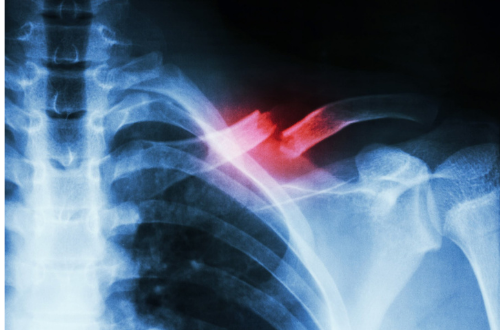

Đây là hình minh họa cho gãy 1/3 ngoài xương đòn

Chụp x-quang là rất cần thiết để xác định gãy xương, vị trí gãy xương, kiểu gãy xương. Bác sĩ có thể yêu cầu chụp toàn bộ vai hoặc lồng ngực. Nếu có gãy xương khác kèm theo thì có thể chụp cắt lớp vi tính để xác định các tổn thương phối hợp kèm theo chi tiết hơn.